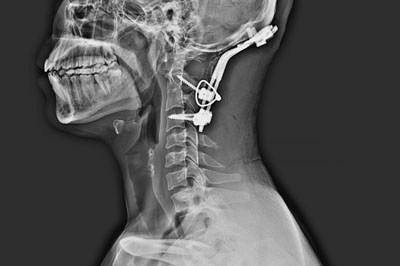

Cervical Spine Surgery

cervical-spine-surgery

Cervical spondylotic myelopathy, cervical disc prolapse and cervical spine fractures are the common problems we encounter in cervical spine region...

Spine fracture

spine-fracture

Fracture in the vertebral body disturbing the continuity in the alignment of back bones. Commonly occurs due to road traffic accident and fall from height...

Fracture in the vertebral body disturbing the continuity in the alignment of back bones is called as spine fracture. Commonly occurs due to road traffic accident and fall from height.

spine-fractures-intro

In simple fracture patient will have back or neck pain .In severe injury patient might have weakness of arms or legs.

Xray is the initial investigation . MRI and CT may be required dependin on the severity of the injury.

The treatment for simple fracture is rest and supportive appliances such as belt/ collar and orthosis. Complex fracture with displacement or with weakness might require surgery for stabilisation.